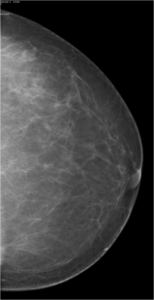

52 year old lady who underwent wide local excision for stage I breast carcinoma of right breast 7 years ago has presented for routine screening mammogram.

Ductal Cell carcinoma In Situ-DCIS RIGHT BREAST.(Comedo and cribriform type)

Craniocaudal and mediolateral oblique views of both the breast.Post operative scar is seen in the upper and outer quadrant of right breast.Pleomorphic calcifications,predominantly showing fine linear branching pattern( comedo pattern) is seen in segmental distribution with nipple convergence in the central right breast.